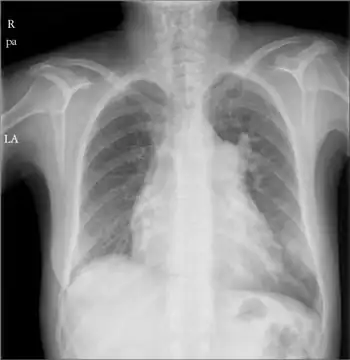

Right atrial enlargement (RAE) is a form of cardiomegaly, or heart enlargement. It can broadly be classified as either right atrial hypertrophy (RAH), overgrowth, or dilation, like an expanding balloon. Common causes include pulmonary hypertension, which can be the primary defect leading to RAE, or pulmonary hypertension secondary to tricuspid stenosis; pulmonary stenosis or Tetralogy of Fallot i.e. congenital diseases; chronic lung disease, such as cor pulmonale. Other recognised causes are: right ventricular failure, tricuspid regurgitation, and atrial septal defect.[1]

It is characterized by a high P wave amplitude (P pulmonale), i.e. a height greater than 2.5 mm in inferior ECG leads (II, III, aVF); and greater than 1.5 mm in right sided precordial leads (V1, V2). [2]